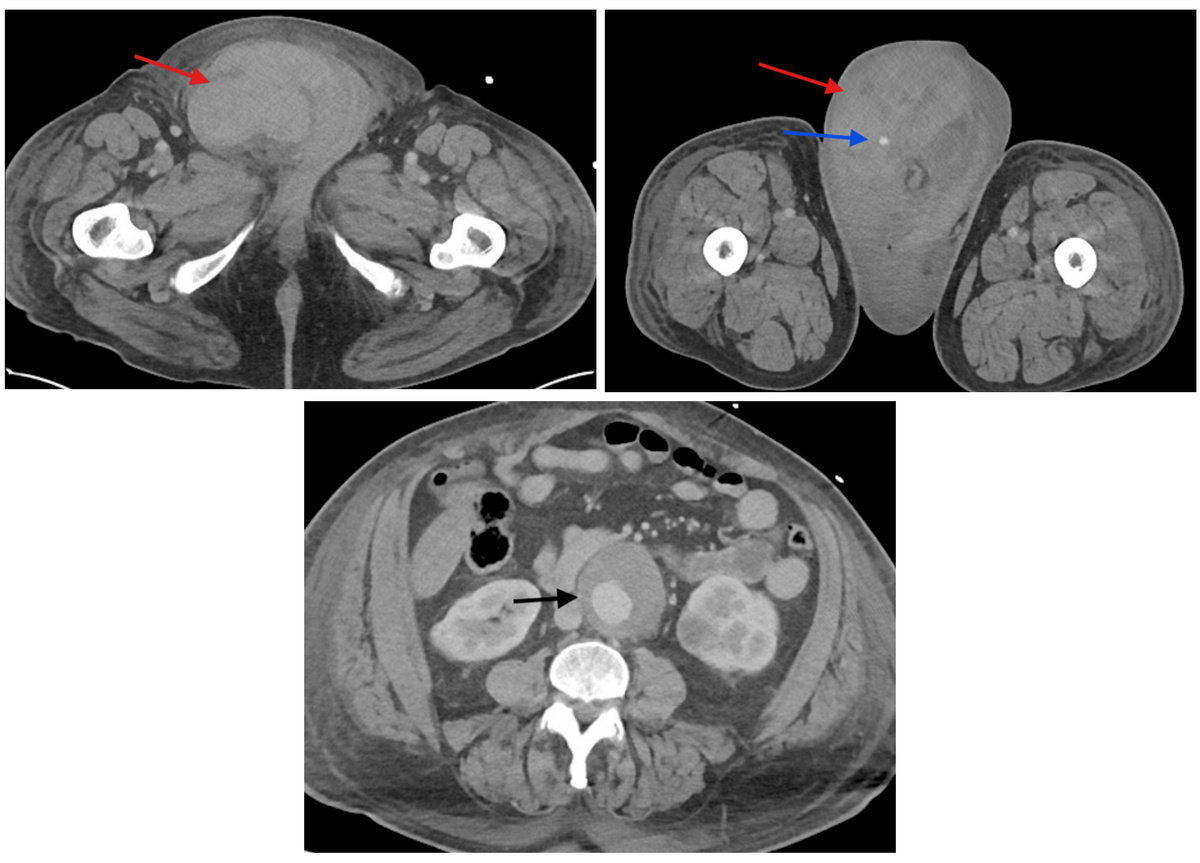

Общий и основной биохимический анализы крови были нормальными за исключением небольшого лейкоцитоза и эритропении. Уровни натрийуретического пептида типа В (показатель дисфункции левого желудочка) и тропонина (маркер инфаркта миокарда) были резко повышены. На ЭКГ были признаки инфаркта миокарда без стойкого подъема сегмента ST. Компьютерная томография с контрастированием выявила крупную гематому правого пахового канала и мошонки, в мошонке также наблюдалось точечное накопление контраста, которое могло свидетельствовать о продолжающемся артериальном кровотечении. Также были случайно обнаружены аневризма брюшной аорты ниже уровня почечных артерий диаметром 6,1 сантиметра и плотное образование в нижнем полюсе левой почки диаметром 3,3 сантиметра — вероятно, почечно-клеточную карциному. На КТ грудной клетки не было признаков легочной эмболии, но визуализировался выпот из-за перегрузки объемом в результате сердечной недостаточности.

Steven J. Laxton, Jackie Dovgalyuk / Cureus, 2025